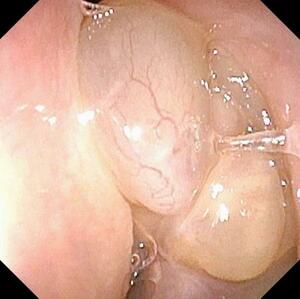

内視鏡で見た好酸球性副鼻腔炎患者の鼻茸(中央や右下の丸く膨らんだ部分)(福井大病院提供)

福井県に住む30代男性Aさんが福井大病院の耳鼻咽喉科・頭頸部外科で好酸球性副鼻腔炎と診断されたのは18年4月。その3年ほど前から鼻詰まりの治療で自宅近くの医院にかかっていたが、鼻の中にポリープ(鼻茸)が見つかったため同病院を紹介された。嗅覚障害でにおいが全く分からず、ひどい...